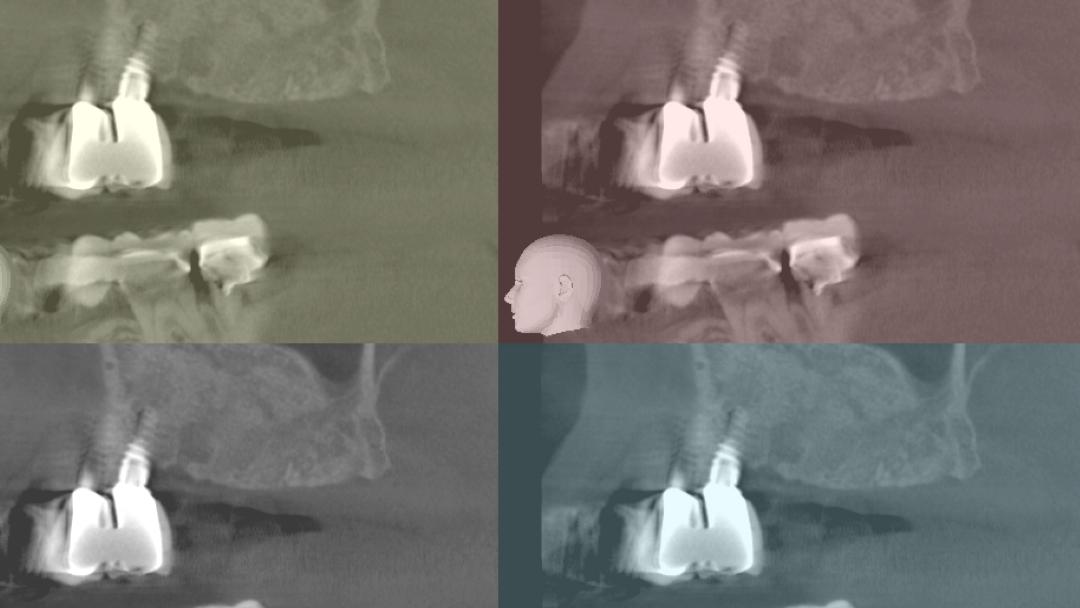

Αυτή η παρουσίαση θα εστιάσει στις επίκαιρες και νέες μεθόδους για την κάθετη αύξηση του οστού, του μαλακού ιστού και του ιγμορείου, και στις ενδείξεις, τα αποτελέσματα και τις επιπλοκές σε ασθενείς με απορρόφηση του φατνιακού οστού και με προσδοκίες σε αισθητικό επίπεδο.

Διαδικασίες βασισμένες σε αποδείξεις που προέρχονται από περισσότερα από 25 χρόνια έρευνας για τα οστικά μοσχεύματα με χρήση διαδικασιών GBR, για τα αυτομοσχεύματα και τα οστικά Fillers θα παρουσιαστούν και θα συγκριθούν με νέες διαδικασίες χρήσης κυτταρικών διαμεσολαβητών οι rh-PDGF and rhBMP-2.

Κλινικές λύσεις για τη βιολογική οστική αναγέννηση και την τοποθέτηση μοσχεύματος στο φατνίο.

Η κάθετη και η οριζόντια πτυχή της αύξησης της ακρολοφίας.

Η βέλτιστη επιλογή σχεδίου, επιφάνειας και θέσης εμφυτεύματος.

Εκμάθηση της χρήσης βιο-υλικών και αυξητικών παραγόντων με αυτογενές οστούν και μεμβράνες φραγμού

1. Οριζόντια αύξηση ακρολοφίας με ταυτόχρονη τοποθέτηση εμφυτεύματος, τοποθέτηση οστικού μοσχεύματος σε στοιβάδες με απορροφήσιμη μεμβράνη & ράμματα στερέωσης

2.Οριζόντια αύξηση ακρολοφίας με τοποθέτηση απορροφήσιμης μεμβράνης, bone tacks & ανάμικτο οστικό Ξενο/Αυτο-μόσχευμα σε αναλογία 1:1

3.Κάθετη αύξηση ακρολοφίας με κυτταροπλαστικές μεμβράνες PTFE με ενίσχυση τιτανίου, οστικές βίδες & ανάμικτο οστικό Ξενο/Αυτο-μόσχευμα σε αναλογία 1:1